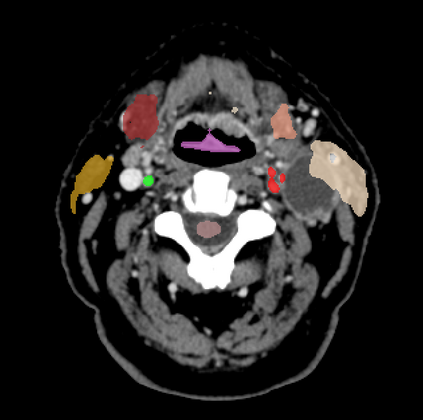

Organ at risk (OAR) segmentation is a critical process in radiotherapy treatment planning such as head and neck tumors. Nevertheless, in clinical practice, radiation oncologists predominantly perform OAR segmentations manually on CT scans. This manual process is highly time-consuming and expensive, limiting the number of patients who can receive timely radiotherapy. Additionally, CT scans offer lower soft-tissue contrast compared to MRI. Despite MRI providing superior soft-tissue visualization, its time-consuming nature makes it infeasible for real-time treatment planning. To address these challenges, we propose a method called SegReg, which utilizes Elastic Symmetric Normalization for registering MRI to perform OAR segmentation. SegReg outperforms the CT-only baseline by 16.78% in mDSC and 18.77% in mIoU, showing that it effectively combines the geometric accuracy of CT with the superior soft-tissue contrast of MRI, making accurate automated OAR segmentation for clinical practice become possible. See project website https://steve-zeyu-zhang.github.io/SegReg